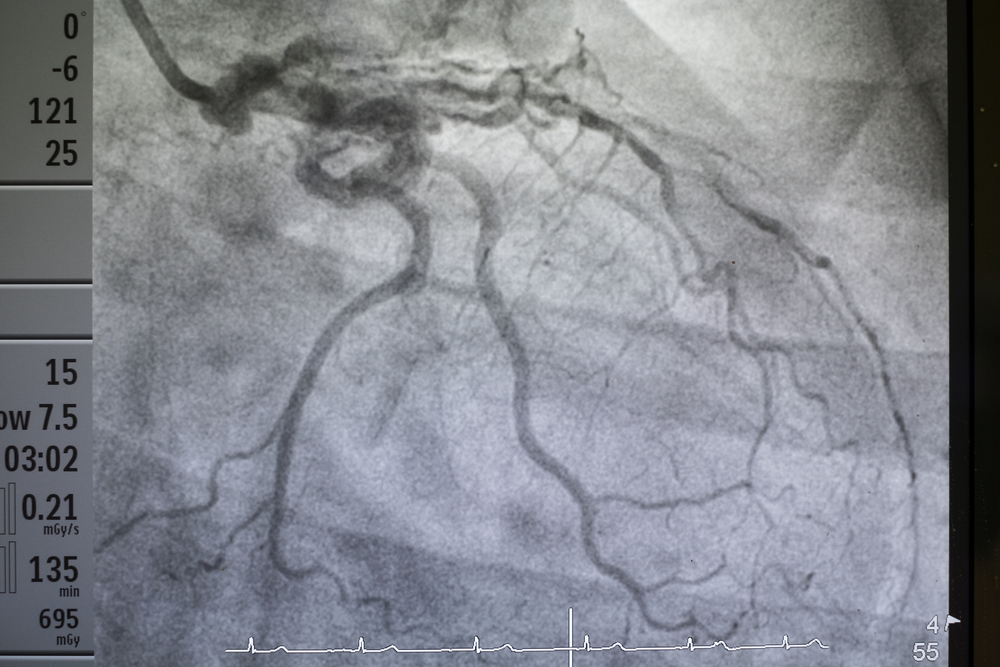

Коронарная ангиография является наиболее распространенным инвазивным методом диагностики в области кардиологии, позволяющим получить детальную информацию о состоянии коронарных сосудов, а также выявить и оценить степень стеноза (сужения) этих сосудов. Процедура осуществляется путем введения катетера в артериальную систему пациента, который аккуратно направляется к сердцу.

Процедура проводится при нормальной работе сердца, когда пациент находится в сознании и лежит на столе. Как только кардиолог достигает коронарных артерий, он вводит контрастное вещество в сосуды, а рентгеновский детектор отображает изображение коронарных артерий на экране в реальном времени. Дозы облучения во время коронарной ангиографии сопоставимы с излучением, получаемым при компьютерной томографии грудной клетки, что эквивалентно примерно 150 стандартным рентгеновским снимкам легких.

Время проведения процедуры составляет около 20 минут, если не возникают осложнения. Одной из ключевых особенностей этого метода является возможность проведения лечебных вмешательств во время коронарной ангиографии, что позволяет не только установить диагноз ишемической болезни сердца, но и сразу же приступить к лечению.

Современные методы визуализации коронарных артерий

Одним из наиболее распространенных методов является коронарная ангиография. Этот инвазивный метод включает введение контрастного вещества в коронарные артерии через катетер, что позволяет визуализировать сосуды на рентгеновских снимках. Коронарная ангиография считается «золотым стандартом» для диагностики коронарной болезни сердца, так как она предоставляет точные данные о состоянии коронарного русла и позволяет одновременно выполнять лечебные процедуры, такие как стентирование.